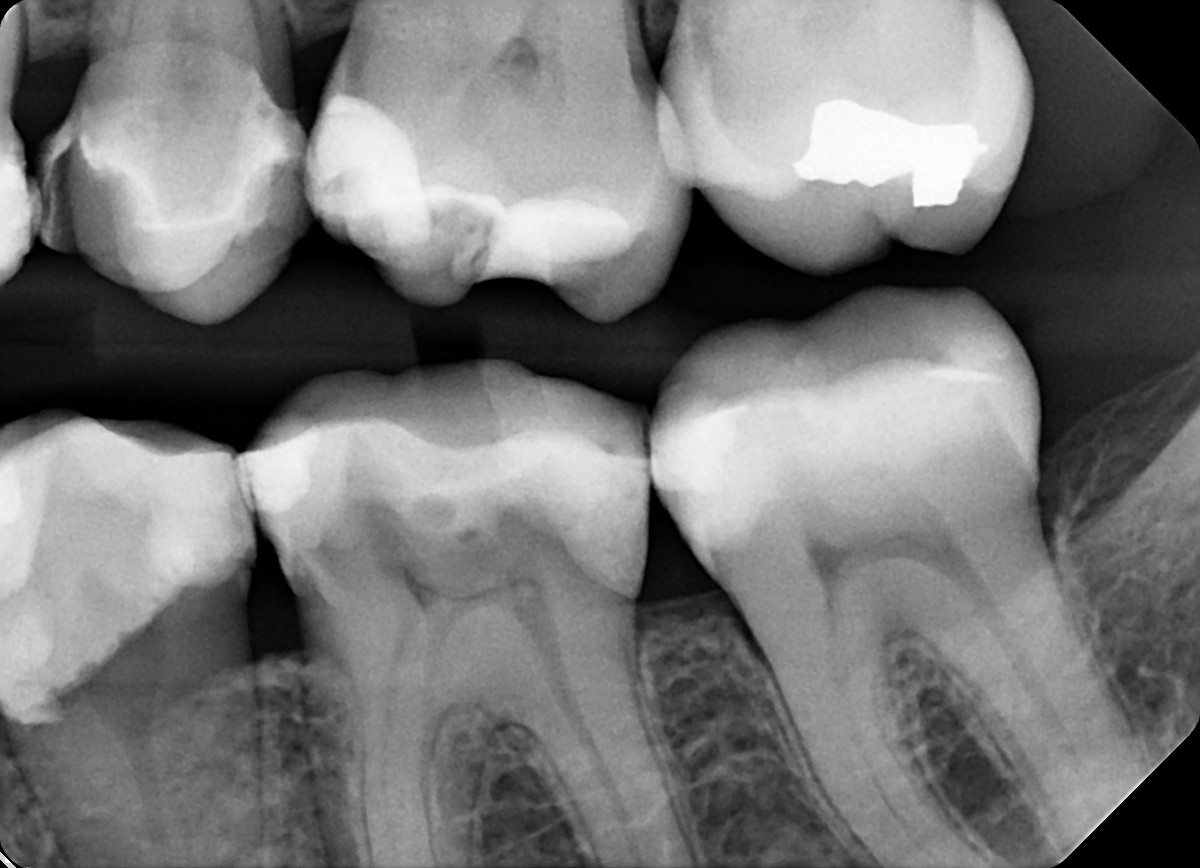

4. In the X ray bellow for which jaw periodontal bone loss is evident?